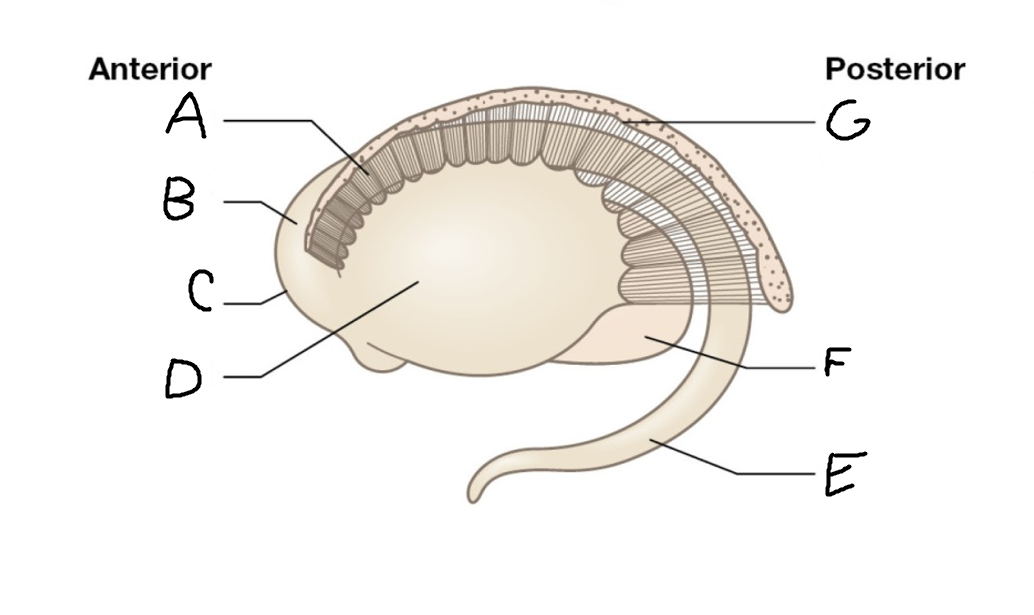

A

caudate nucleus head

C

caudate tail

D

globus pallidus (internal segment)

E

globus pallidus (external segment)

F

putamen